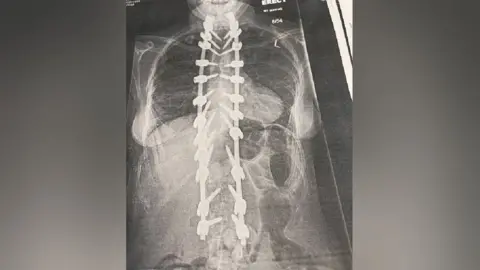

The surgery though was a success, with surgeons completing the final part of the procedure by inserting two titanium rods into her spine, to pull her back as far as possible to straighten her back.

"I'm 7cm taller now and I've had to buy a whole new wardrobe."